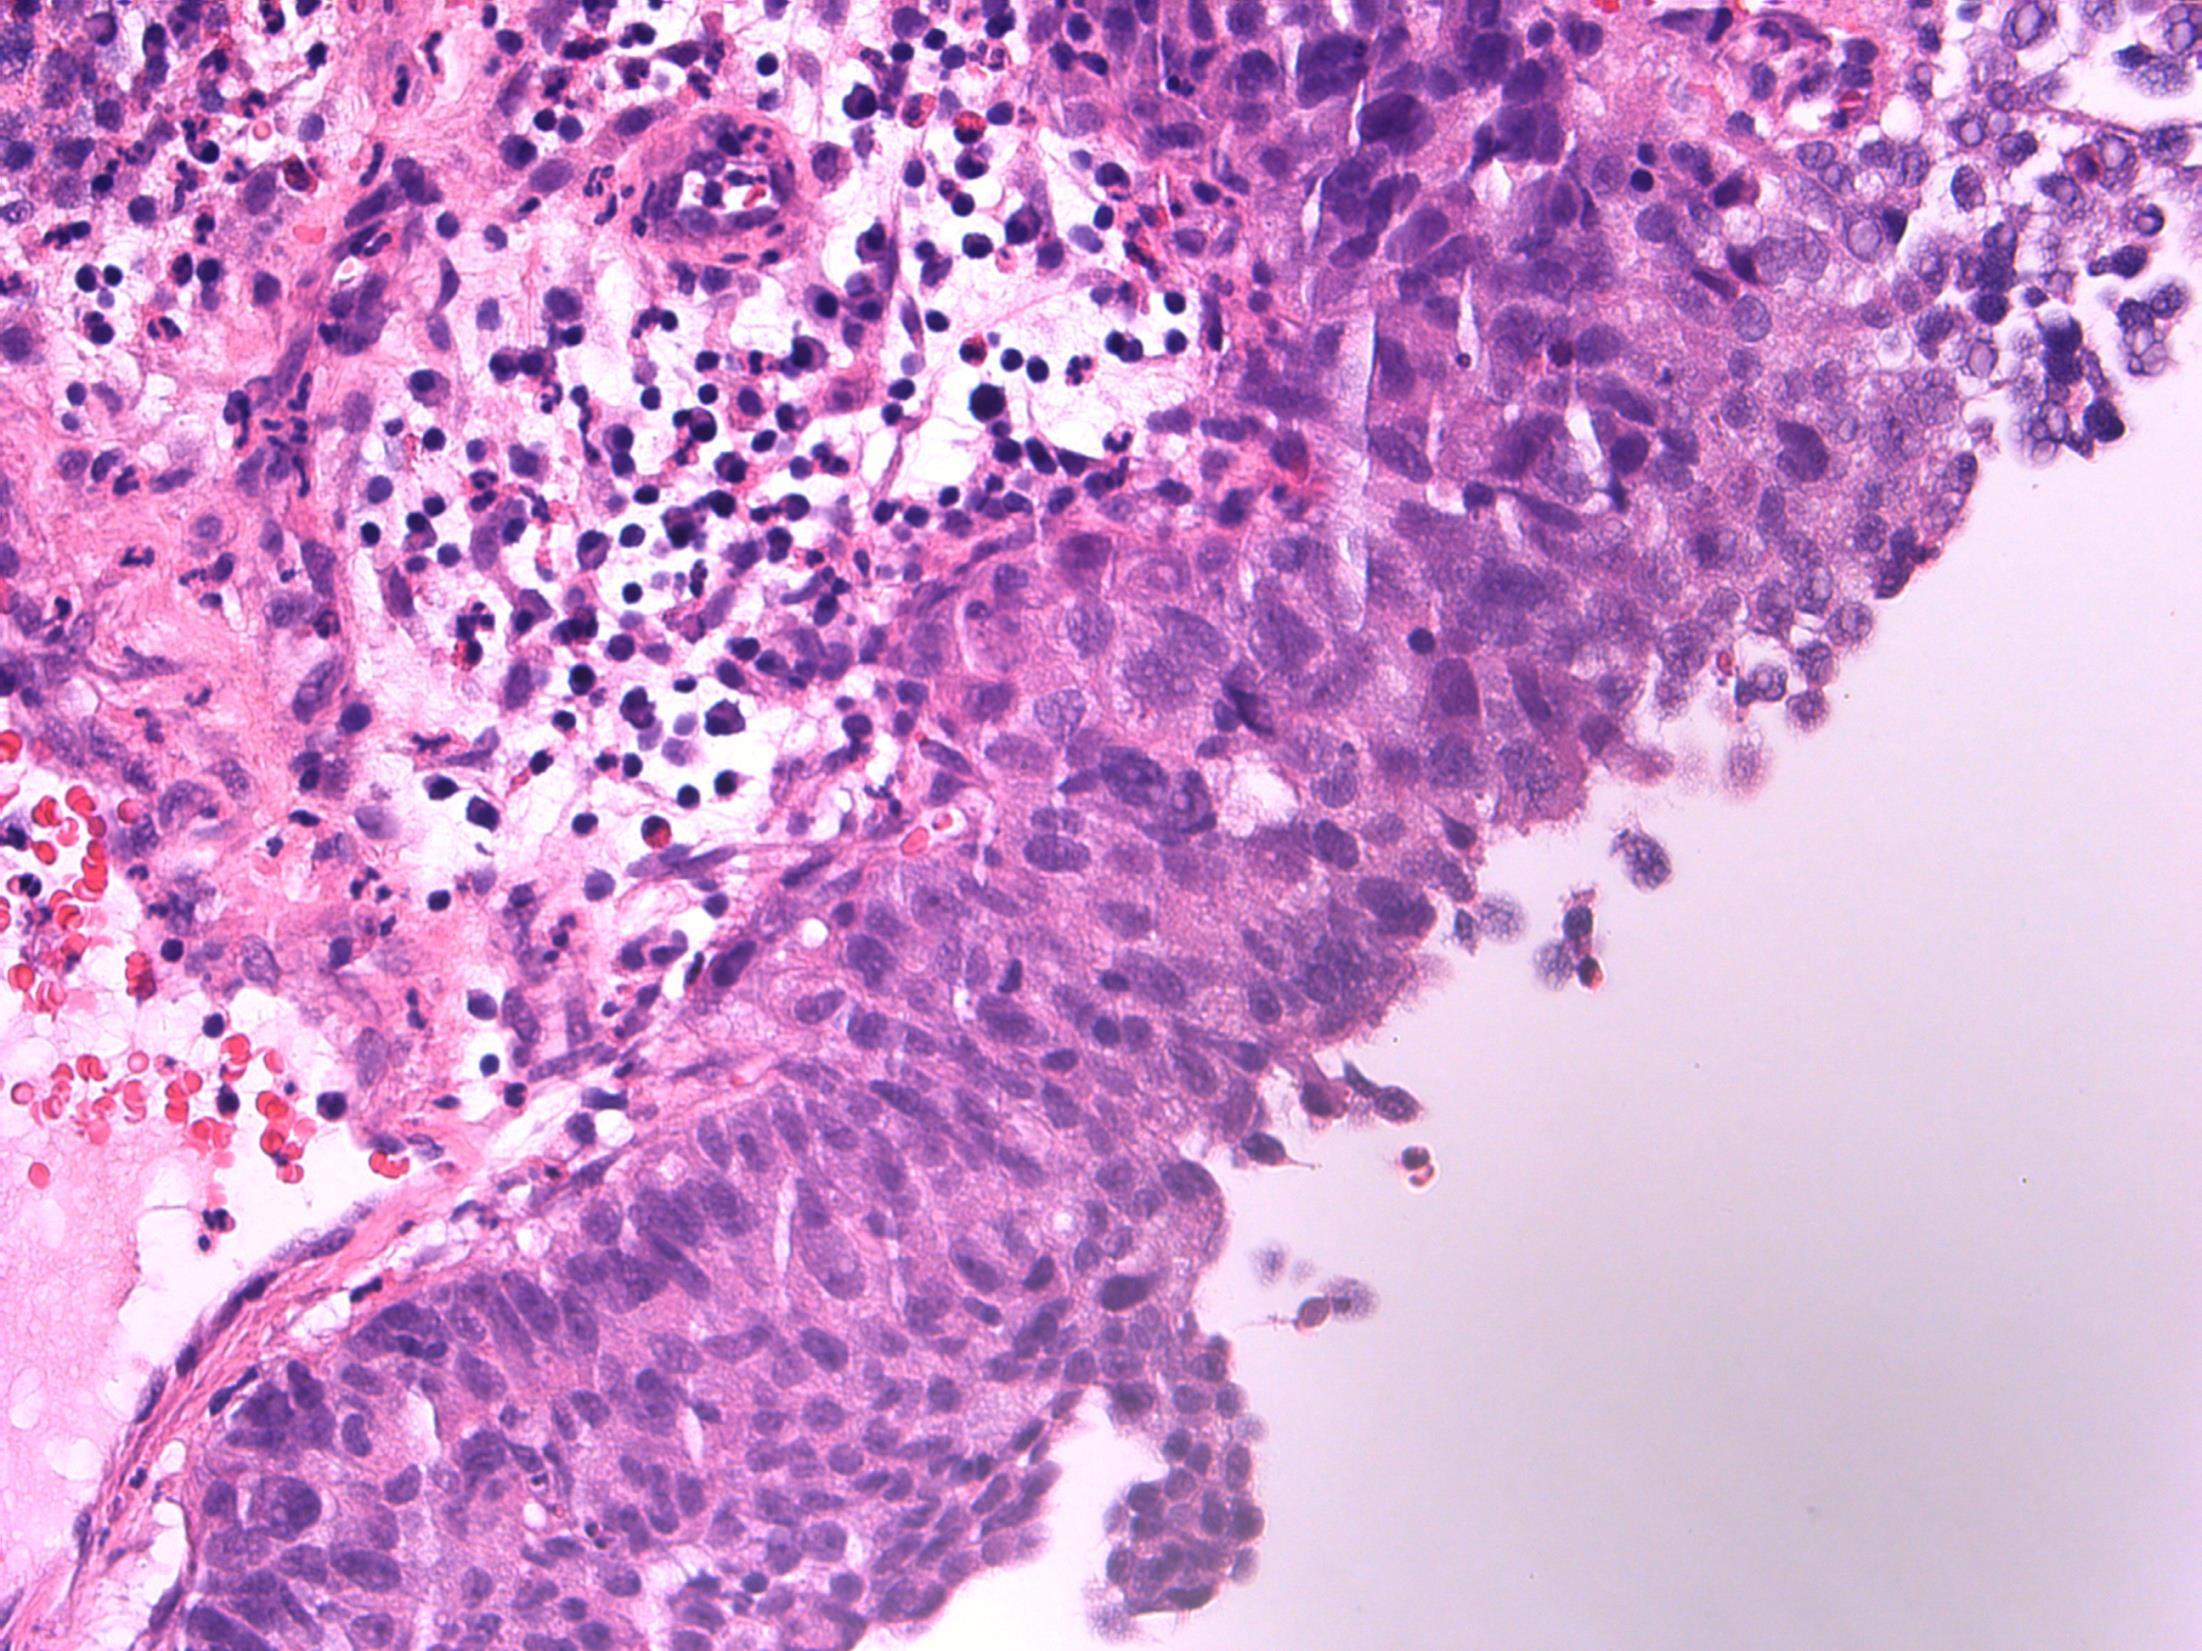

• 80F, with haematuria. Cystoscopy shows a large tumour on the posterior wall. TURBT performed.

TURBT - G3 (high-grade) TCC with small cell carcinoma component

Description: Biphasic malignant tumour. High grade large epithelial cell component and high grade small round blue cell tumour component. CIS also seen.

Favoured Diagnosis: G3 (high-grade) TCC with small cell carcinoma component. Plan: Correlate with urine cytology/ previous biopsies. IHC: TCC= AE1/3+, p63+, small cell ca = AE1/3 dot +, CD56+, synapto +. Look for invasion into lamina propria and muscle (staging).

Comments: • Small cell carcinoma is frequently admixed with TCC, SCC or adenocarcinoma of bladder • >90% muscle invasive and metastases common, poor prognosis. • Responds to chemotherapy (cisplatin based) • Differential Diagnosis of pure small cell carcinoma: – Poorly-differentiated urothelial carcinoma – Metastatic small cell carcinoma from other site eg lung – Lymphoma – Alveolar rhabdomyosarcoma – Inflammation (in a crushed, cauterised, superficial or scant specimen)

3.5 Associations, prognosis, treatment etc 3.0 Use of IHC for confirmation 2.5 Description with diagnosis, mentions both components 2.0 Only one component mentioned 1.5 Other malignant diagnosis 1.0 Benign diagnosis Case 5